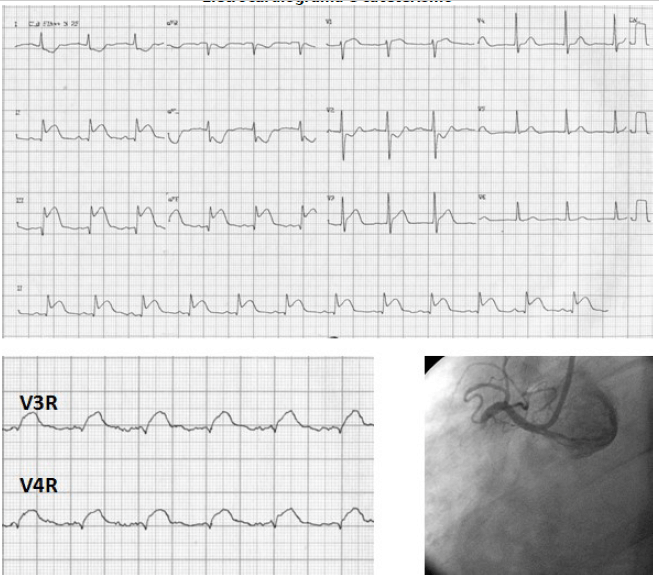

Paciente hipertensa e diabética deu entrada no ponto atendimento, apresentando dor torácica em aperto, associada a náuseas. No hospital, foi diagnosticado com síndrome coronariana aguda e levado ao cateterismo.

Eletrocardiograma e cateterismo

Enunciado 1145332-1

Em relação a paciente acima, qual droga deve ser evitadas nesse paciente: